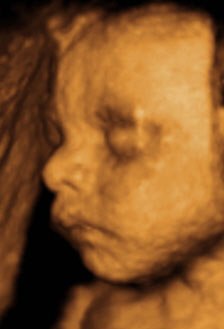

Kan da lige sætte et par billeder ind fra i mandags, hvor jeg var 27+5 uger henne, så du kan se kvaliteten

Vedhæftede fotos (klik for at se i fuld størrelse)